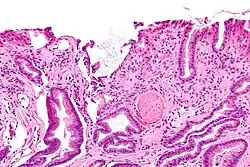

La GAVE se caracteriza por capilares dilatados en la lámina propia con trombos de fibrina. El principal diagnóstico diferencial histomorfológico es la hipertensión portal, que a menudo se manifiesta a partir de los hallazgos clínicos.